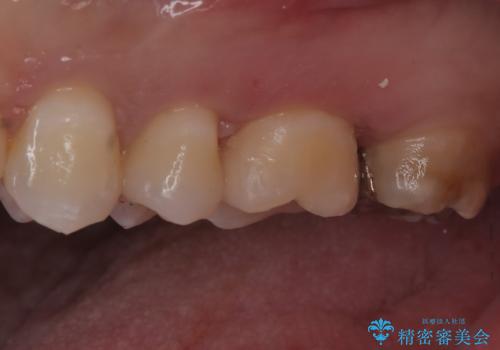

- 定期健診にて虫歯を見つけたためセラミックインレーにて修復しました。

綺麗に仕上がり患者さんも非常に満足されていました。

当院でのセラミックインレーはラバーダム防湿をして接着しております。